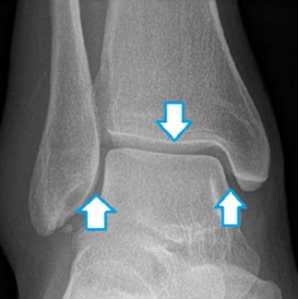

Важно отметить, что рентген применяется не только для определения тех или иных видов переломов, но и с целью выявления повреждений синдесмоза.

![8]()

Рис. 8 Форма вилки голеностопа полностью соответствует форме таранной кости. При этом, ширина щели сустава (отмечена стрелками) одинакова с каждой стороны.